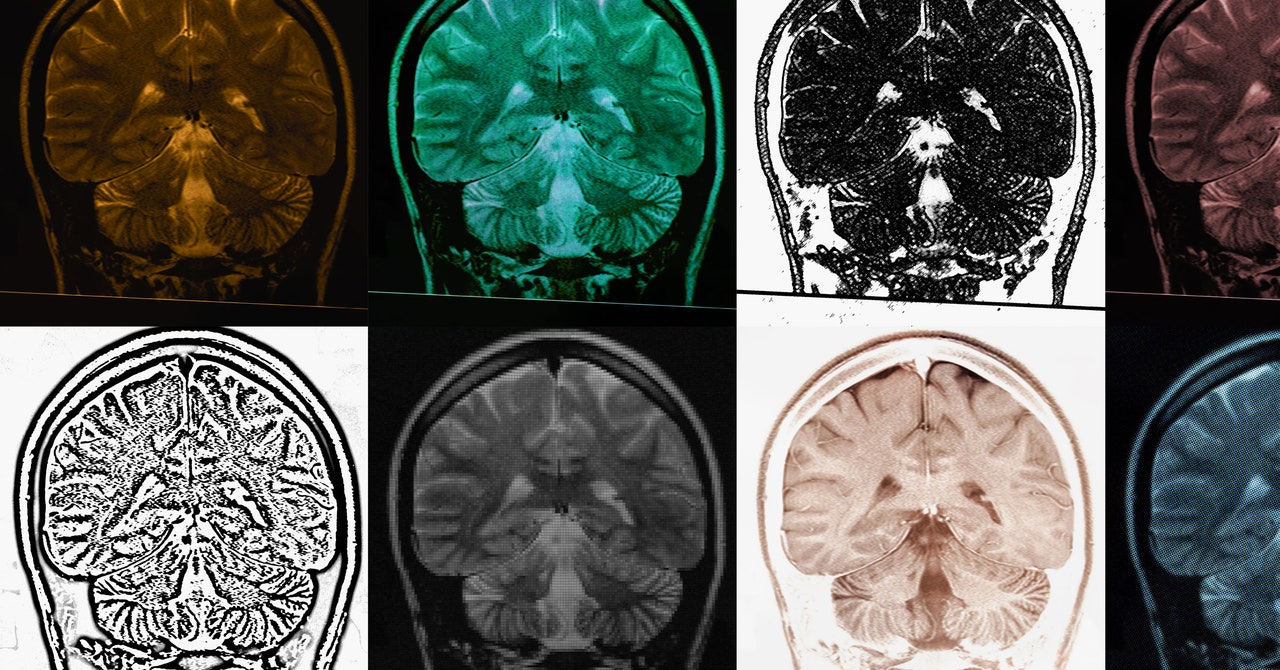

A new study using PET scans has found that autistic individuals have fewer synapses in their brains, which correlates with more pronounced autism traits such as social and communication difficulties. This discovery marks the first time synaptic density has been measured in living autistic individuals and could revolutionize diagnostic and treatment approaches, potentially leading to more targeted interventions. The research highlights the importance of understanding the biological underpinnings of autism to improve support and quality of life for those on the spectrum.